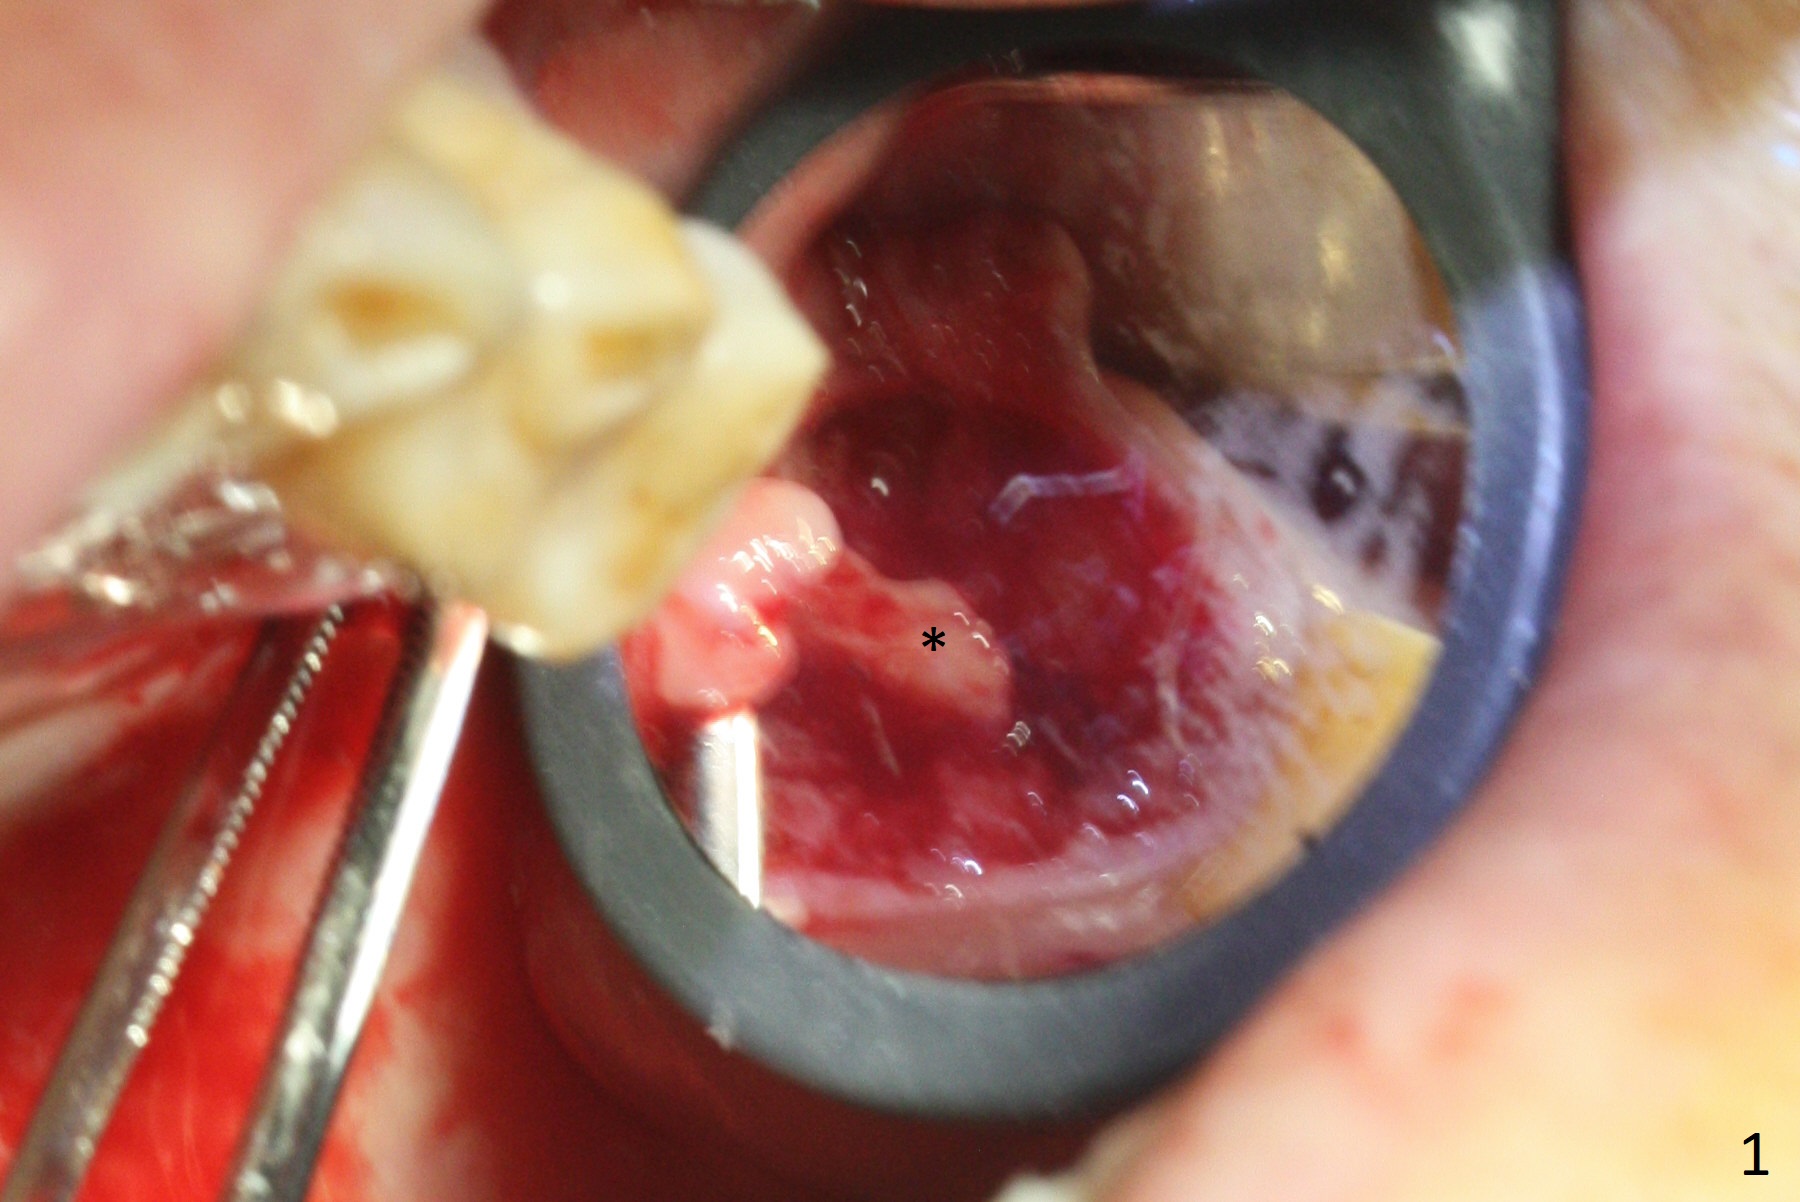

The septum is found to be pointed after extraction of the tooth #14 (Fig.1 *). The septum is flattened with Rongeur (Fig.2 *) prior to osteotomy. Because of interference of the mesial bone (Fig.3 *), osteotomy does not reach the depth with use of stopper. Without the latter, a 5x11.5 mm implant barely penetrates the sinus floor (Fig.4 (no postop nasal hemorrhage)). Also due to the mesial bone interference, a 6.5 mm abutment is not seated. Finally a 5.5x7(5) mm abutment is placed for an immediate provisional. Periodontal dressing is applied to cover the buccal repaired gingiva (Fig.5 *). There is minimal thread exposure after removal of the provisional nearly 2 months postop (Fig.6). The provisional does not return for easy self cleansing. In fact this is not an easy task, because of the posterior position (Fig.8 (after Piezo scaling)). The distal implant remains exposed; the abutment is removed and a healing screw is placed (Fig.9). The implant should have been subcrestal distally (Fig.7 <, nearly 3 months postop). One month later, the implant seems to be buried (Fig.10). The straight abutment is changed to an angled one (4.5 x15 degree A (5) mm) before impression retake (Fig.11,12 (<, dashed line: access hole)). The implant should have been placed more mesial (Fig.13). Surgical guide is needed. There is no implant exposure clinically or in CBCT sections 1 year 2 months post cementaton (Fig.14), although 3 D image suggests missing distopalatal plate (Fig.15).